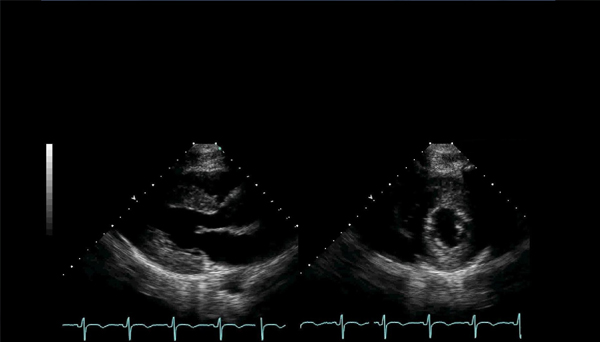

Adult Echocardiography

Adult echocardiography is a non-invasive ultrasound test used to examine the heart's structure and function in adult patients. It helps cardiologists assess heart conditions such as valve disorders, heart failure, cardiomyopathies, and congenital heart defects

This diagnostic tool uses sound waves to create real-time images of the heart, providing valuable insights into the heart's chambers, valves, and blood flow.